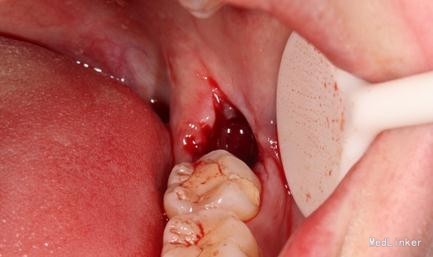

患者女,25 主诉: 要求拔牙。 现病史: 3天前,患者感左下后牙疼痛,食物嵌塞,咀嚼不适。自服消炎药后好转,前来就诊。 既往史: 体健,否认药敏史。

检查: 18.28颌面龋坏,质地软,牙颈部脱矿,叩诊(-),不松动。 37玻璃充填物,叩诊(-),不松动,冷热刺激正常。 38近中水平阻生,牙龈无红肿,叩诊(-),探诊有盲袋,盲袋内食物碎屑。 47缺失多年,48近中向移位,间隙1mm,叩诊(-),不松动。

治疗计划:18、28,38拔除。 37重新充填。 48观察。 治疗:28局麻下拔除。 38阻滞下拔除。